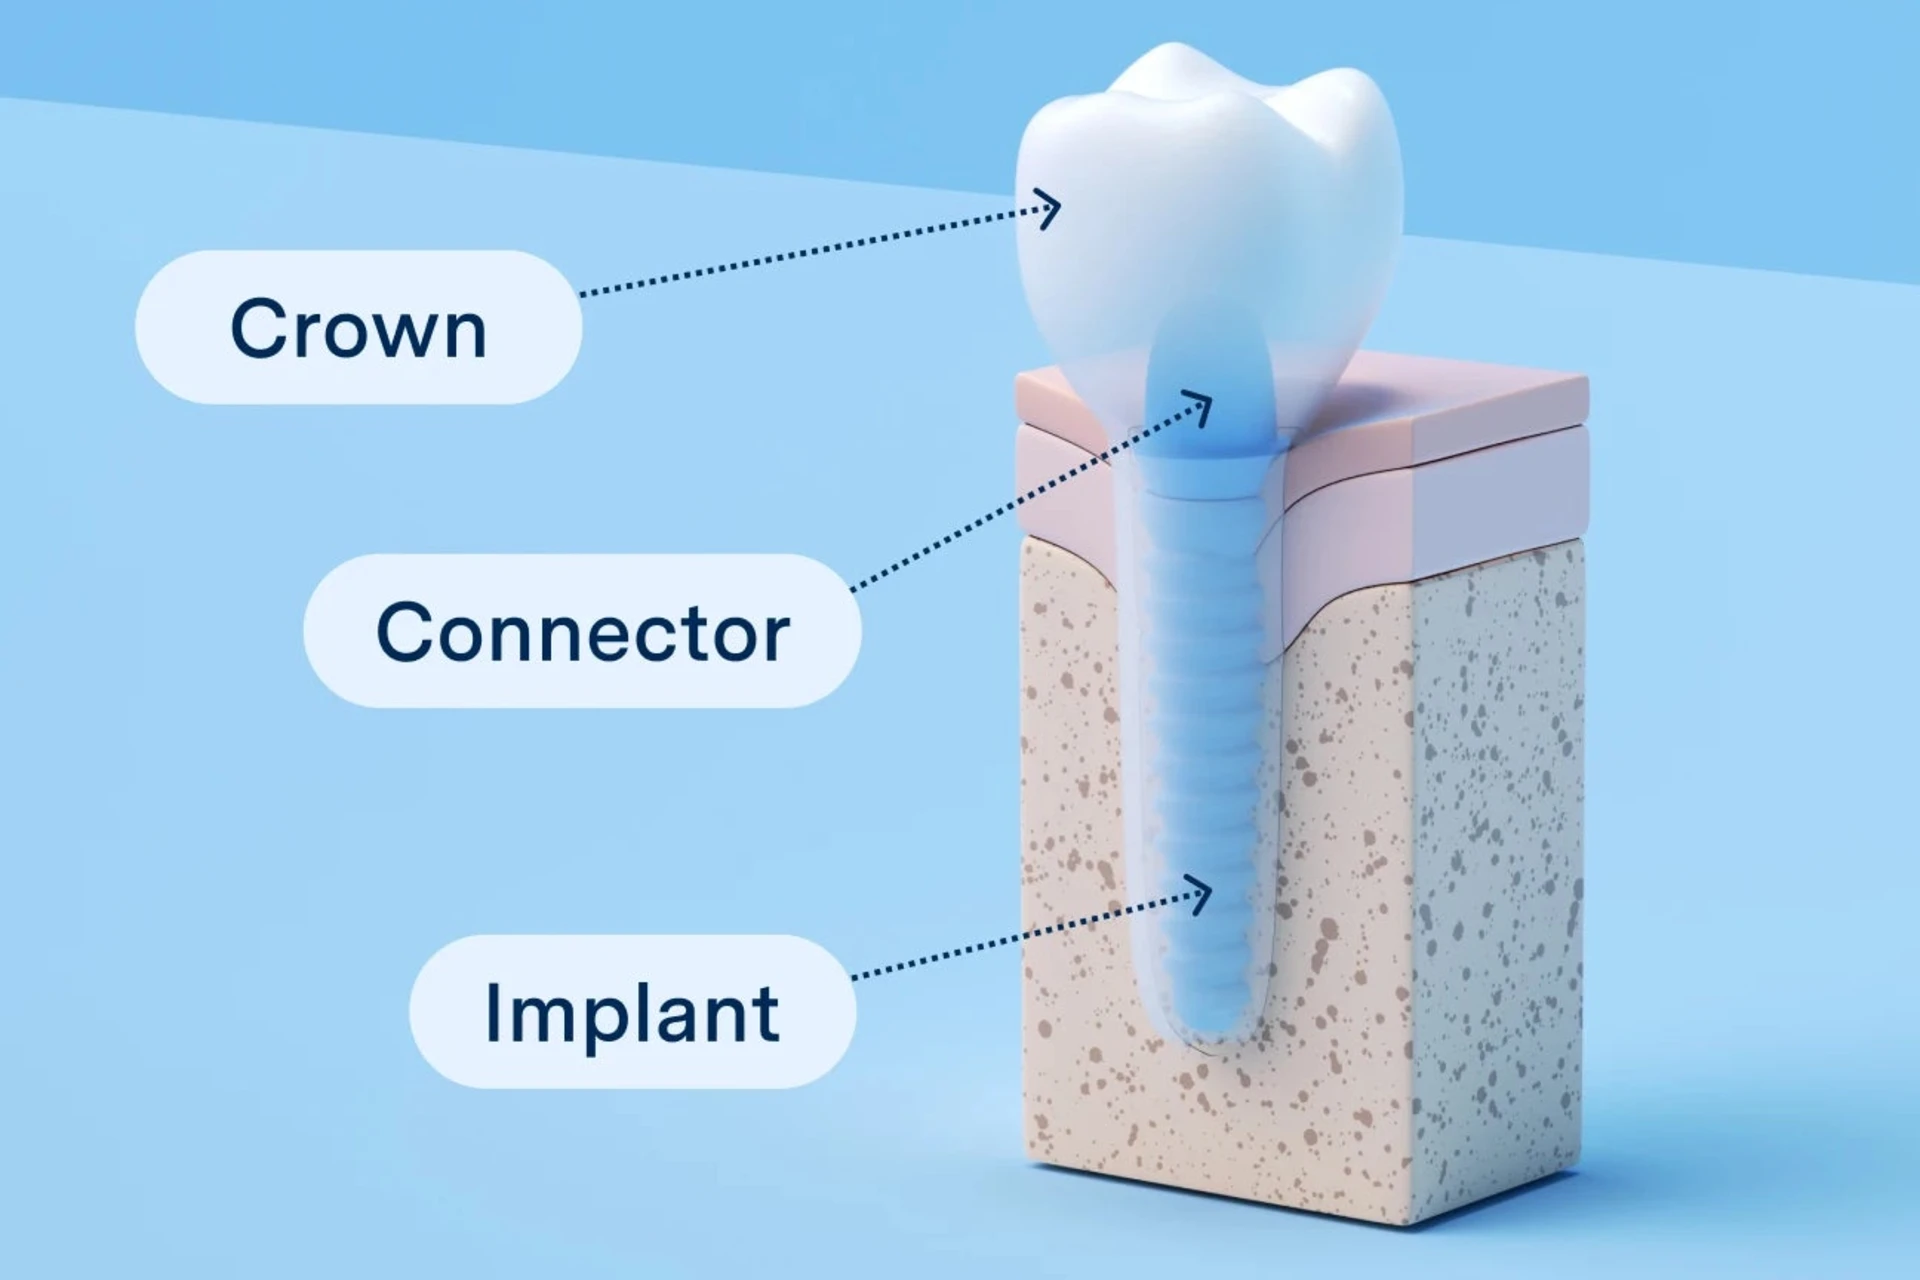

Dental implants the best permanent solution for tooth loss. So while their upfront costs may be higher than alternative tooth-replacement solutions, they are your best solution for replacing teeth long-term. The cost of implants may vary based on several factors, including additional procedures like extractions, bone grafts and the materials chosen. Austin Emergency Dental prioritizes affordability and offers competitive pricing, ensuring personalized smile solutions are within reach. Schedule a consultation with our experienced clinicians for a detailed cost estimate on implants tailored to your needs, and take the first step toward restoring your smile.